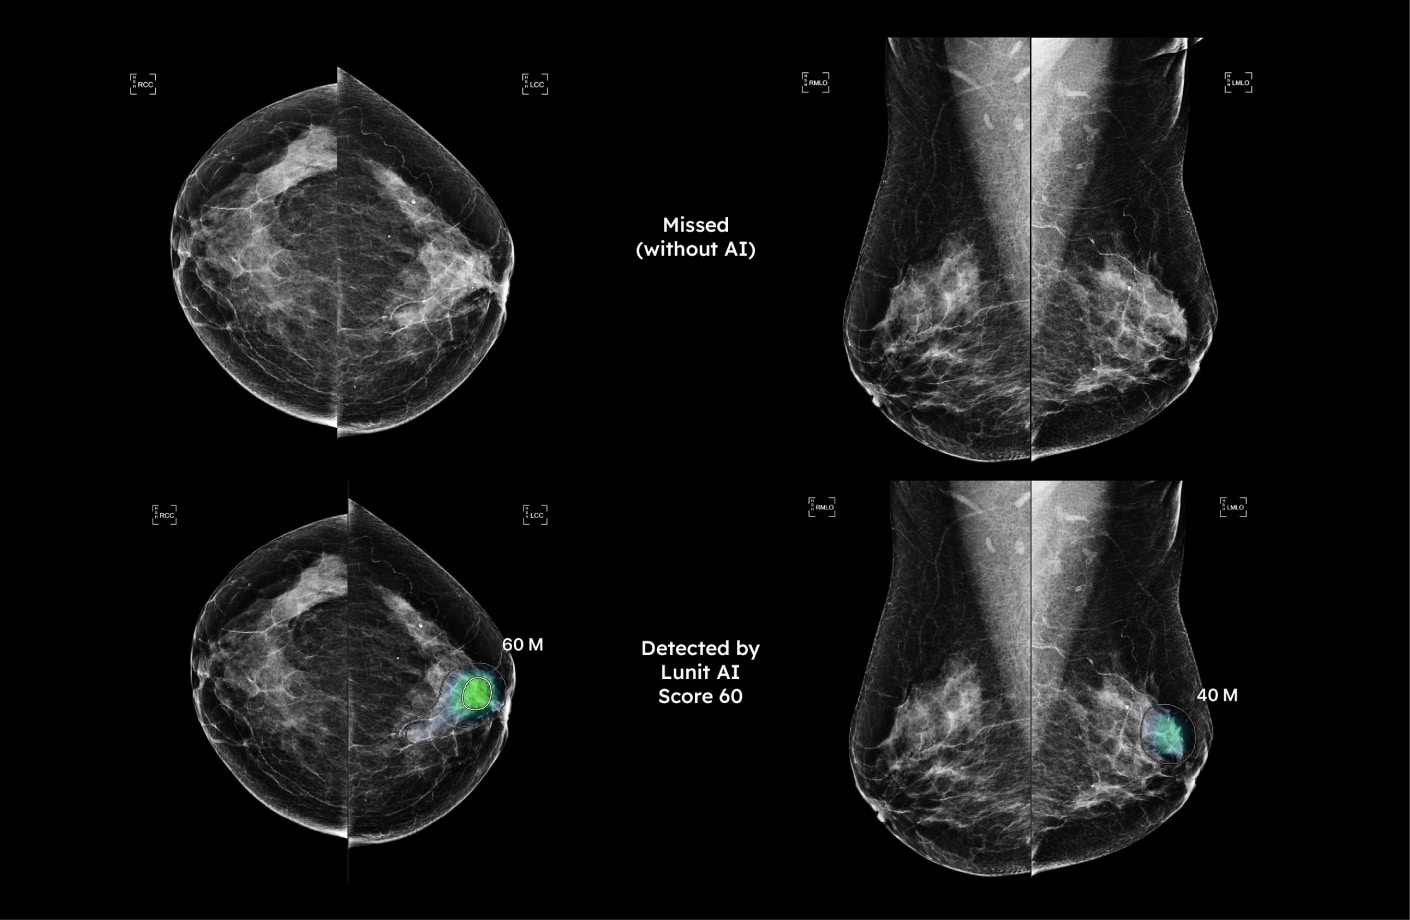

루닛 인사이트 MMG는 유방 촬영 영상을 분석해 유방암 의심부위의 위치와 유방 내 병변이 존재할 가능성을 0~100 범위의 점수로 표시합니다.

JAMA Oncology에 발표된 연구에서 루닛 인사이트 MMG는 악성 병변 탐지에서 우수한 정확도와 민감도-특이도의 균형 잡힌 성능을 보인 것으로 나타났습니다.2